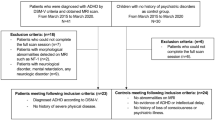

Children with ADHD and a control group of children without ADHD were recruited from the outpatient clinic of the Child and Adolescence Psychiatry Department at Seoul National University as well as from Jung-gu Mental Health Welfare Center in Seoul. The inclusion criteria for the ADHD group were as follows: (1) ages 6–12, (2) previously diagnosed with ADHD according to Diagnostic and Statistical Manual of Mental Disorders fifth edition (DSM-5) and Schedule for Affective Disorders and Schizophrenia for School-Age Children-Present and Lifetime Version (K-SADS-PL). Meanwhile, the inclusion criteria for the control group were as follows: (1) ages 6–12, (2) not diagnosable with any child psychiatric disorder according to psychiatric interviews and K-SADS-PL.

The exclusion criteria for both groups were as follows: (1) Diagnosed with congenital genetic disease, (2) a history of prominent acquired brain injury such as cerebral palsy, (3) diagnosed with epilepsy, neurologic disease, or untreated sensory disorder, (4) history of schizophrenia or psychosis, (5) diagnosed with obsessive–compulsive disorder, major depressive disorder, or bipolar disorder, and (6) diagnosed with language disorder or severe learning disorder. Both groups were also divided into the same three age groups: 6–7, 8–9, and 10–12. Group division into every year would be ideal, but the number of participants was limited in this study. Therefore, 2–3 year grouping of participants was considered reasonable in this study.

We recruited 157 children with ADHD (mean age, 8.15 ± 1.75 years; male: 123; female: 34) and 109 children without ADHD (mean age, 8.65 ± 1.68 years; male: 56; female: 53) (Table 1). All of the 157 children in the ADHD group and the 109 children in the control group were classified into subgroups of ages 6–7, ages 8–9, and ages 10–12, and CBF was compared and analyzed between age groups. In the ADHD group, there were 70 participants aged 6–7, 53 aged 8–9, and 34 aged 10–12; in the control group, there were 33 participants aged 6–7, 39 aged 8–9, and 37 aged 10–12 (Table 2). There were 10 ADHD participants with tic disorder, 5 ADHD participants with oppositional defiant disorder (ODD), and 9 ADHD participants and 1 control participant with other mild mood or anxiety disorder (Table 1). Also, there was 1 ADHD participant who was taking medication during the study. The portion of participants with tic disorder or ODD as comorbidities and of participants taking medication was considered negligible during analysis.